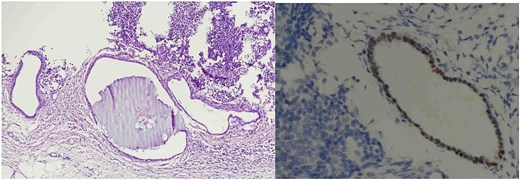

Histopathological analysis showed two reactive lymph nodes measuring 2.0 cm and 3.5 cm. Immunohistochemistry demonstrated positivity for pancytokeratin, estrogen receptor (ER), and CD10, consistent with endometrial tissue. Histopathological images of the lymph nodes are presented in Figs 1 and 2. No signs of malignancy were identified.

Lymph node endometriosis. Lymph node number 1, A: Hematoxylin/eosin stain × 40; B: Estrogen receptor immunostaining × 200.